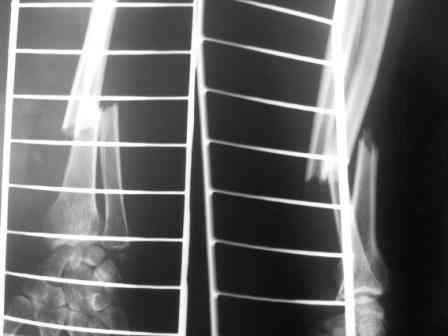

Еще бы потом не забыть рентгенограмму из цветной сделать полутоновой в серой шкале, да и сжатие можно посильнее. файл станет меньше.

Согласен с допонением. Но делаем это не всегда, т.к. стараемся сохранять все снимки пациентов (получается много), а обработку проводим уже по нужным изображениям.